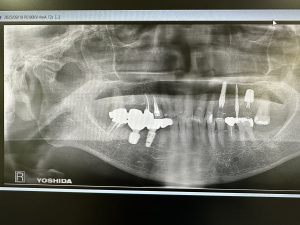

本日は昼からインプラントオペ

昨年右下オペした方

今回は反対側の上顎3.6番

2本抜歯、6番はソケットリフト、いわゆるデンサーリフト💪

計測値も良く、一安心